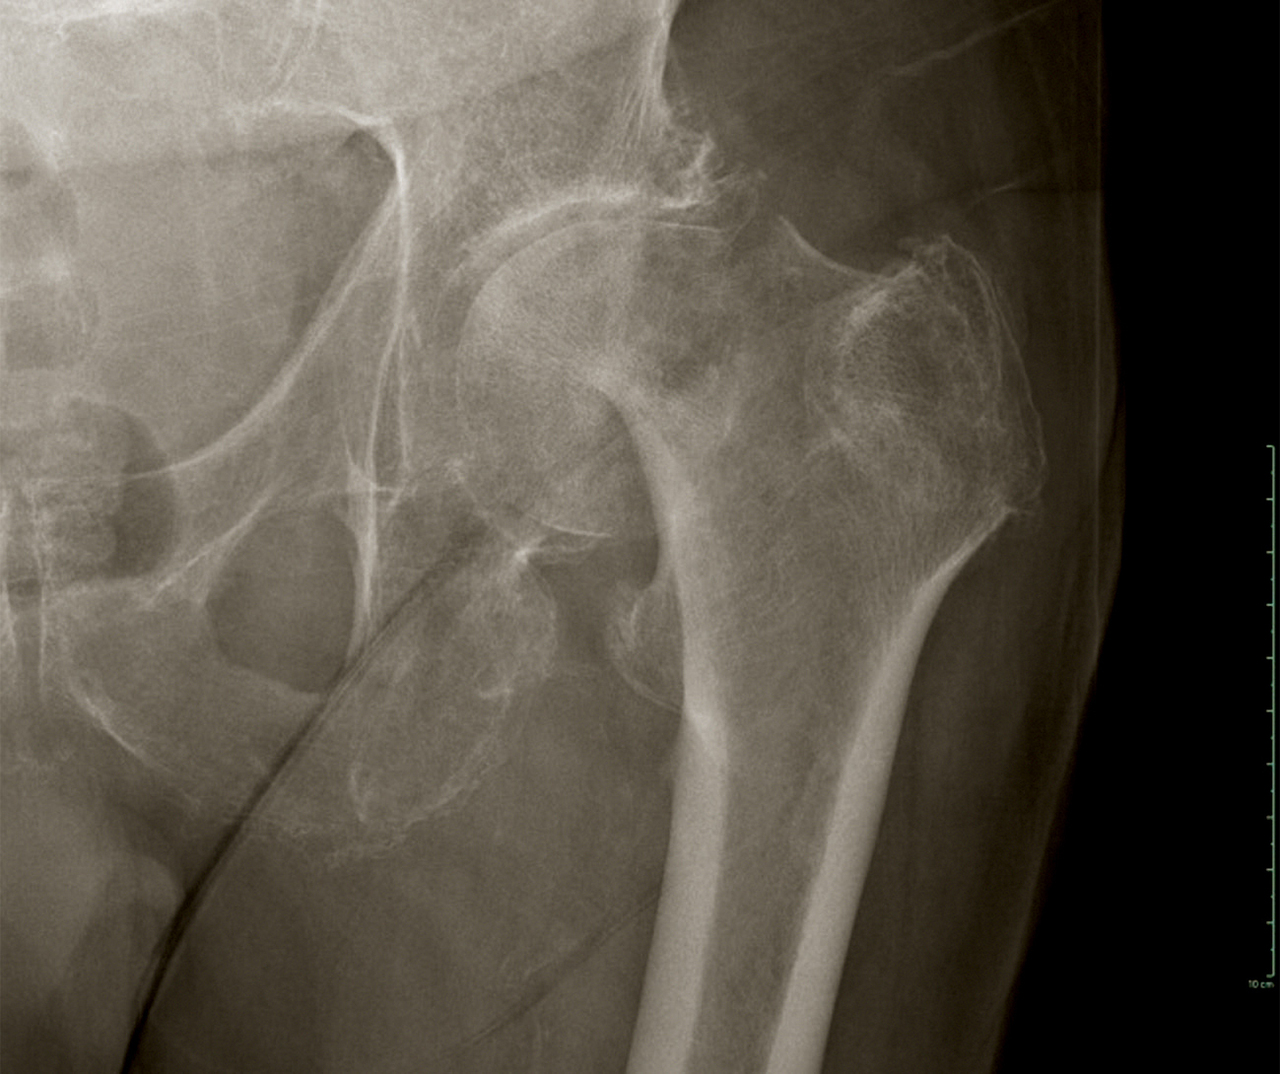

Voici la radiographie de face.

Figure 1

Question 4 – Quel est votre diagnostic ?

Une déformation du membre inférieur comme décrite ne peut être qu'une fracture du col du fémur, de type Garden 3 ou 4, ou une fracture du massif trochantérien.